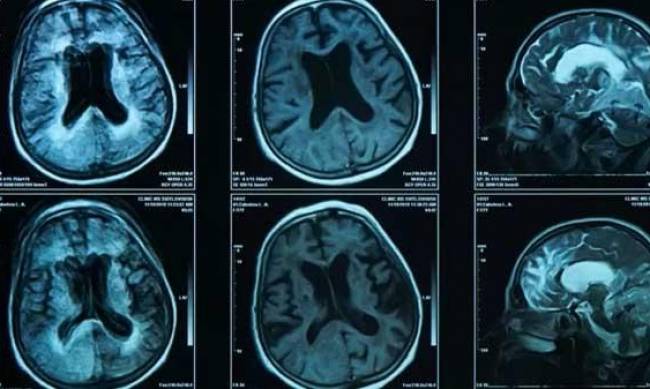

Як вік впливає на мозок?

Об’єм мозку з часом зменшується. У здорових людей найбільше втрачає із віком префронтальна кора. Вона зменшується приблизно на 5% за десятиліття.

Ця ділянка - своєрідний "диригент" мозку, який виконує складну керівну функцію, поєднуючи когнітивні процеси в інших частинах.

Вона відіграє ключову роль у питанні лідерських здібностей, тому що вона залучена у таких процесах, як розвʼязання проблем, постановка цілей і контроль імпульсів.

Керівна функція поступово знижується протягом 30 років і прискорюється після 70 років. Так звана "хвороба білої речовини" – різні стани, спричинені пошкодженням білої речовини мозку, – також знижує керівну функцію.

Вона вражає приблизно третину людей віком 65 років і старше. Керівна дисфункція може проявлятися у зниженому контролі імпульсів і частішому повторенні думок та поведінки.